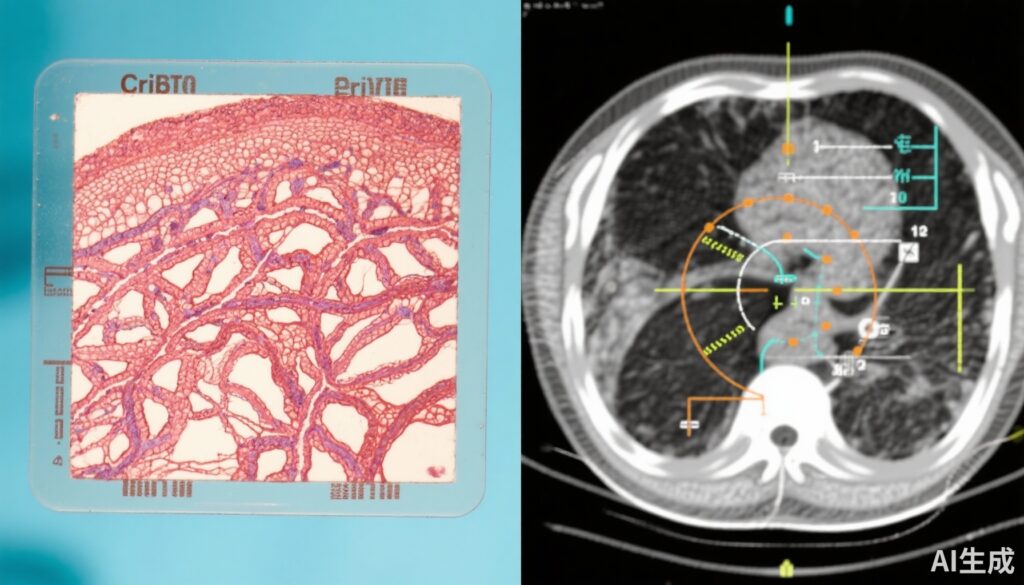

前列腺癌是全球男性中最常见的恶性肿瘤之一。组织病理学特征,特别是筛状结构——包括侵袭性筛状癌和导管内癌——一直与侵袭性肿瘤行为和不良临床结果相关。尽管其预后意义已知,但筛状阳性前列腺癌的最佳管理策略尚未确定,尤其是缺乏评估这种亚型长期转移风险的随机临床试验数据。

PROTECT试验是一项从1999年到2009年进行的标志性3期随机临床试验,共纳入1,643名临床局限性前列腺癌患者。参与者被随机分配接受三种管理策略之一:主动监测、根治性前列腺切除术(手术)或放疗联合新辅助雄激素剥夺治疗(ADT)。这项二次分析回顾性地审查了712名患者的活检标本,这些标本可用于集中组织病理学评估。如果诊断活检切片中发现侵袭性筛状癌和/或导管内癌,则将患者分类为筛状阳性。主要终点是在15年内进展为转移性疾病,包括通过影像学或PSA水平超过100 ng/mL确认的骨、内脏或淋巴结转移。进行了意向治疗和按方案分析,调整了年龄、PSA水平、Gleason评分和治疗分配等关键变量。